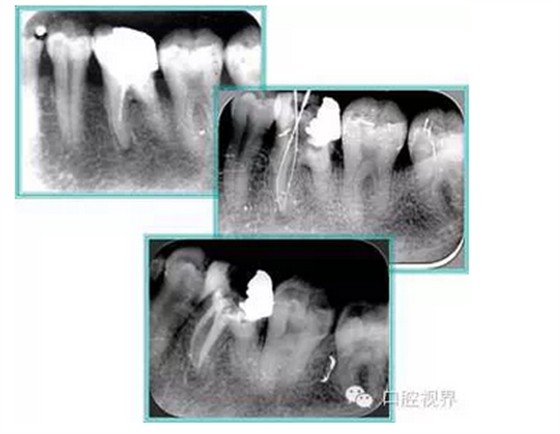

7. 器械折斷

右圖及下圖為器械折斷的 X 線片。箭頭處示折斷器械。

解決方法: ( 1 )取出。 ( 2 )通過。 ( 3 )重新確定工作長度,充填。 ( 4 )根尖手術(shù)。

器械折斷可以不用取出,取出的原因多是患者心理因素。留在里面的器械關(guān)鍵是進行消毒,預(yù)防性使用抗感染藥物,預(yù)防感染。

右圖箭頭處示臺階形成。